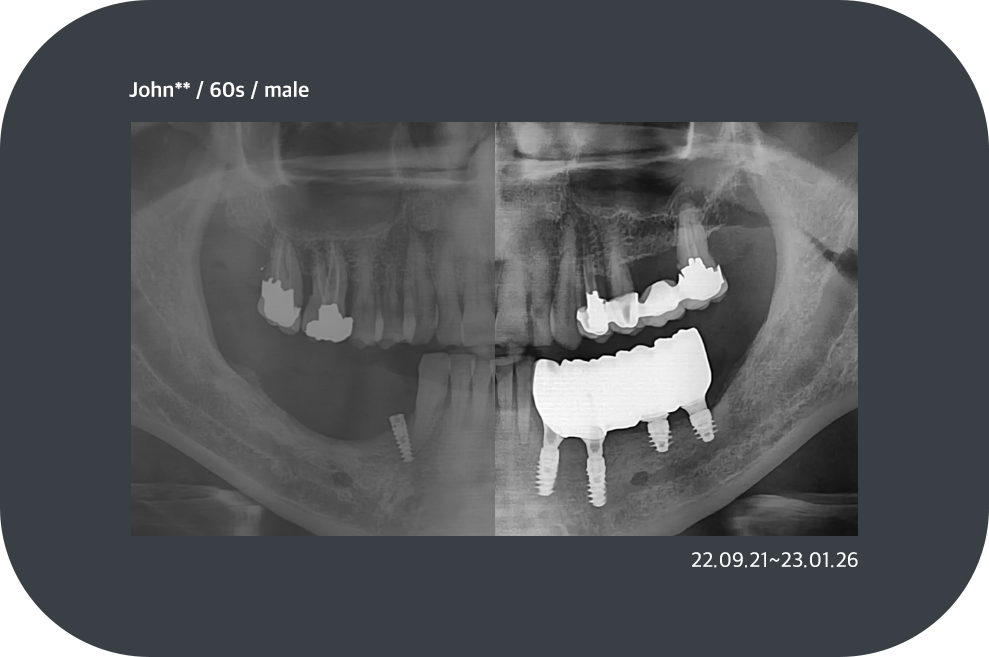

치료사례

임플란트 치료사례

implant_case01

implant_case02

implant_case03

implant_case04

*모든 증례 사진은 의료법 제23조, 제56조에 의거하여, 당사자의 동의하에 게시하였습니다.

*치료 사진은 모두 본원에서 치료한 환자분의 사진입니다.

*치료 사진은 모두 동일인의 사진이며, 동일조건에서 촬영하였습니다.

*개인의 차이에 따라 시술 및 수술 후 부작용이 발생할 수 있으며, 의료진과 충분한 상담을 받으시기 바랍니다.